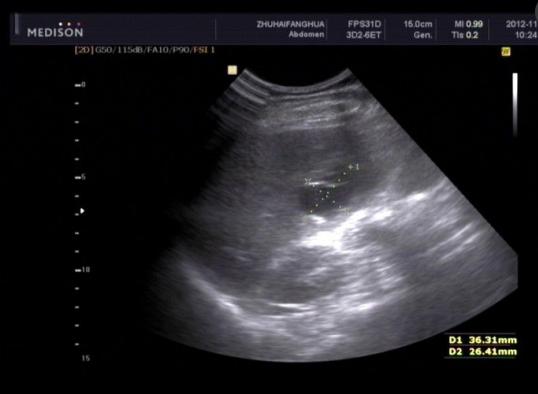

2.用X线检查,尤其是立位腹平片,通常可以发现膈下是否有游离气体。

3.用B超,CT检查等。